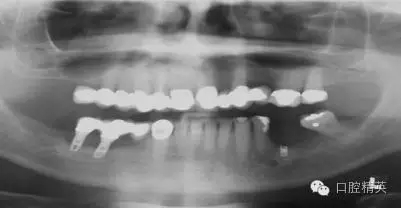

圖7a:6,7號牙種植體(3*15mm)折斷前,從物理學理論上講,種植體骨整合后,基臺螺絲和種植體相連接的支點處是受力時種植體最薄弱的位置。(a)可見6號牙種植體的折斷面,和7號牙種植體上的折裂線(b)。

圖7b:6,7號牙種植體折斷后。

種植體折斷可能發(fā)生于種植體行使功能幾年后,也可能發(fā)生于早期。(圖7a,b)對于圖中這一病例,治療計劃是在對患者的咬合關系,未來修復體理化環(huán)境,患者咀嚼習慣等充分評估后制定的。種植體折斷后,對該病例進行了回顧性病因分析,上了頜架的模型揭示了過長的頜間距離,和嚴重、廣泛的對頜牙磨耗(圖7c,d)。對于這一病例,醫(yī)生仔細評估了所有可得到的回顧性診斷信息,和患者進一步討論交流后,提出了幾個診斷建議和一個過渡性治療方案,其中包括將固定修復改為鑄造可摘局部義齒。